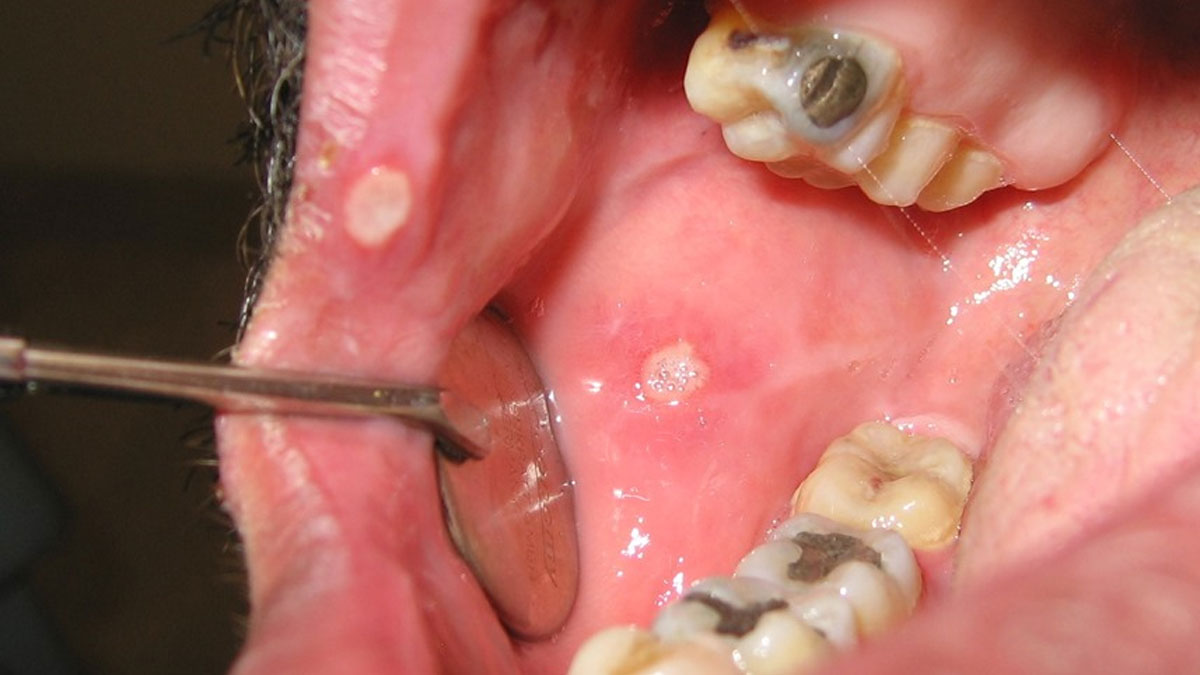

آفت عودکننده دهان؛ علل، تشخیص و روش های درمانآفت عودکننده دهان یکی از شایعترین زخم های دردناک دهانی است. در این مطلب با علائم، دلایل بروز آفت و روشهای جدید درمان آن از جمله لیزر آشنا شوید. ...